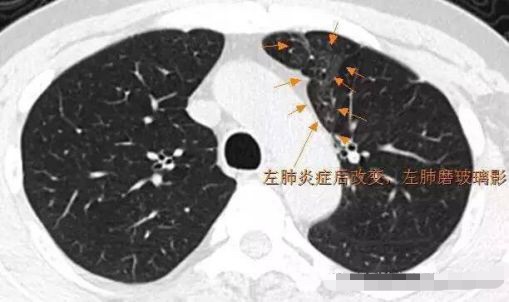

8.元芳,这是肺内炎症后改变 可以看得出明显的肺泡样结构。这种都是良性表现,依靠医生的火眼金睛才能分辨。

9.元芳,这个是肺内炎症后吸收改变,逐步缩小的病史证实其为良性病变